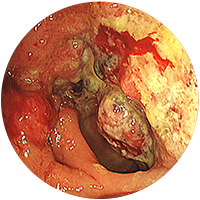

-

2

진행성대장암